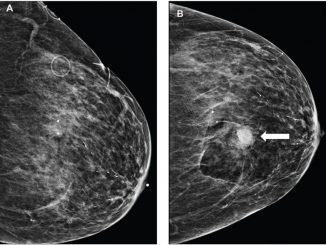

Bleeding after image-guided breast biopsies: Discontinuing vs. maintaining antithrombotic therapy

According to a study published in the American Journal of Roentgenology (AJR), frequencies of imaging-apparent and palpable hematoma were not […]